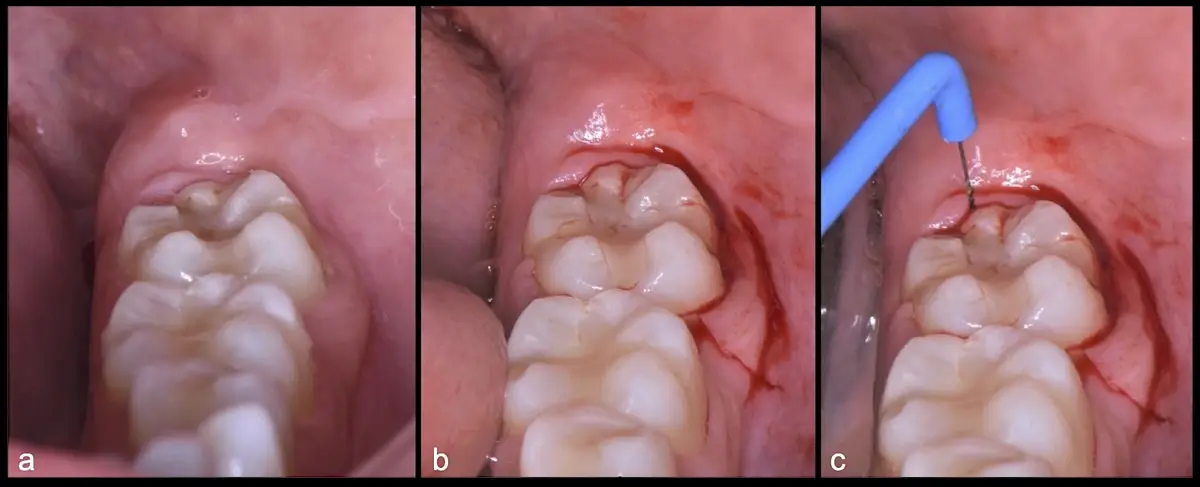

Figura 15. Vista clínica de la pieza 3.8 retenida (a). Incisión intrasulcular vestibular y distal e incisión vertical por mesial de 3.7 (b). Incisión horizontal en dirección distal de la pieza 3.7 con punta de corte del electro bisturí (c).

Figura 16. Cauterización con inserto de punta de coagulación del electro bisturí (a). Elevación del colgajo (b). Osteotomía con el inserto plano de corte de punta aserrada del piezoeléctrico (c).